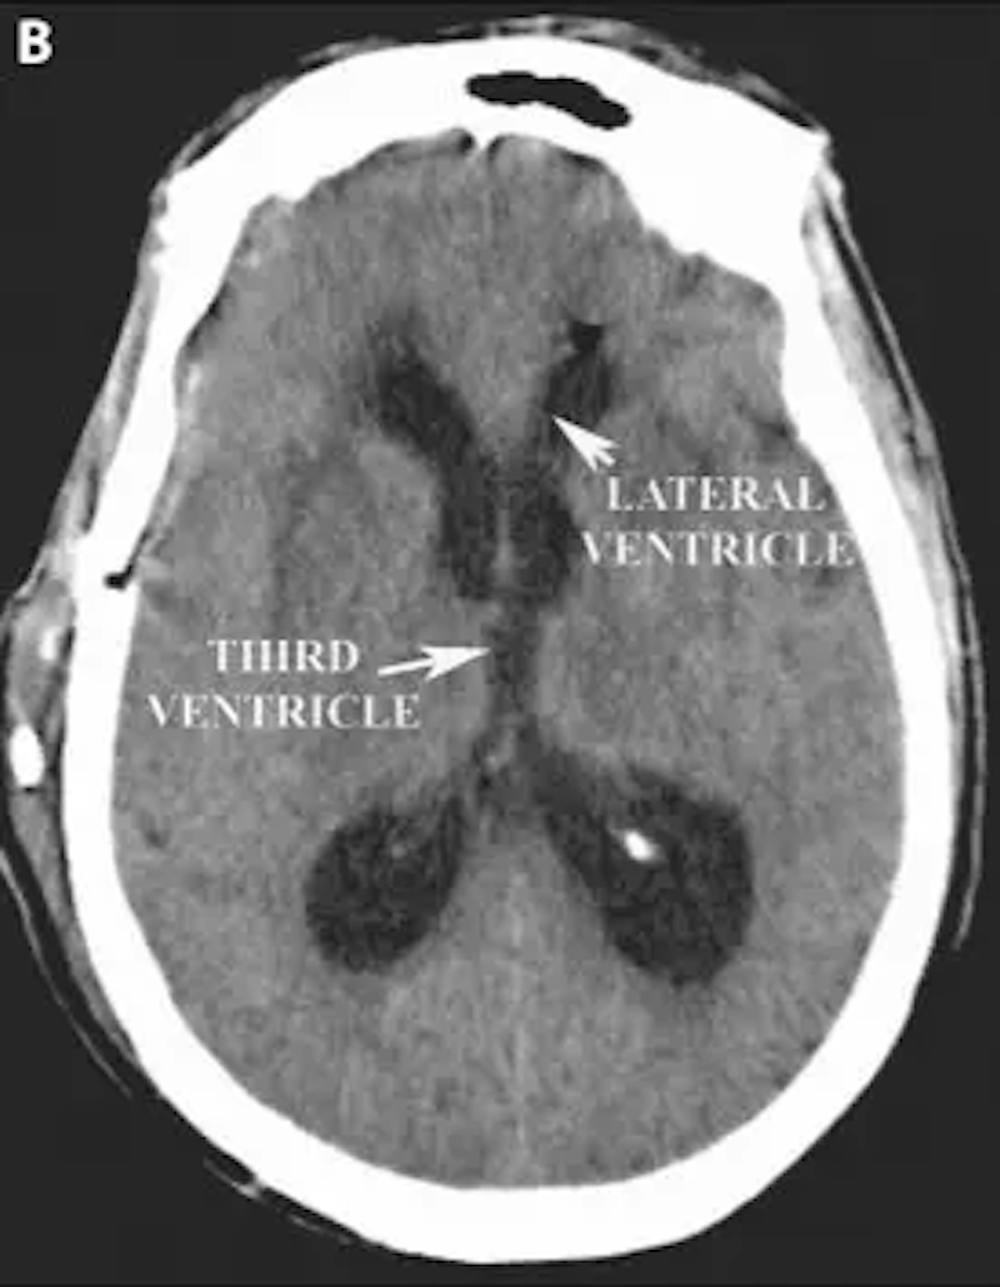

ب) التصوير المقطعي المحوسب للرأس المحوري بعد العملية الجراحية يُظهر انخفاضًا في حجم البطينين الجانبي والثالث بعد وضع التحويلة.